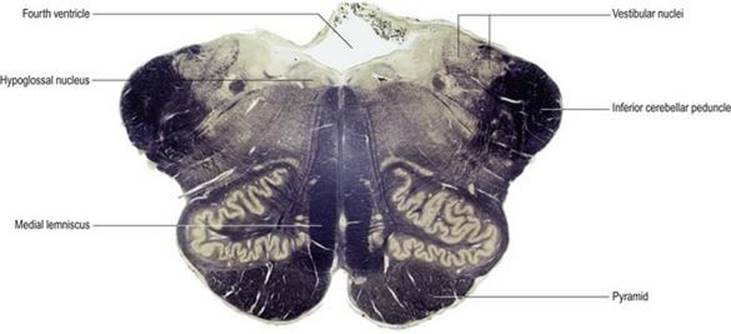

شکل ۱.۵ بخش تاجی از طریق مغز که توزیع ماده خاکستری و سفید را نشان میدهد. این بخش با تکنیک مولیگان رنگ آمیزی شده است که ماده خاکستری را آبی رنگ میکند و ماده سفید را نسبتاً بدون رنگ میگذارد.

شکل ۱.۵ بخش تاجی از طریق مغز که توزیع ماده خاکستری و سفید را نشان میدهد. این بخش با تکنیک مولیگان رنگ آمیزی شده است که ماده خاکستری را آبی رنگ میکند و ماده سفید را نسبتاً بدون رنگ میگذارد.

شکل ۱.۱۹ مقطع عرضی از طریق ساقه مغز در سطح بصل النخاع برش به روش وایگرت پال رنگ آمیزی شده است. نواحی غنی از فیبرهای عصبی تیره رنگ میشوند در حالی که نواحی غنی از بدن سلولی نسبتاً کم رنگ تر هستند. این هرم شامل فیبرهای حرکتی نزولی است که از قشر مغز به نخاع میروند. لمنیسکوس داخلی شامل آکسونهای صعودی است که اطلاعات حسی را از اندامها به مراکز بالاتر در مغز حمل میکند. پایه مخچه تحتانی حاوی الیاف نخاعی مخچه ای است که اطلاعات را از مفاصل و ماهیچهها به مخچه منتقل میکند. هستههای دهلیزی محل خاتمه عصب دهلیزی هستند. هسته هیپوگلوسال محل منشاء رشتههای عصبی هیپوگلاس است.

شکل ۱.۱۹ مقطع عرضی از طریق ساقه مغز در سطح بصل النخاع برش به روش وایگرت پال رنگ آمیزی شده است. نواحی غنی از فیبرهای عصبی تیره رنگ میشوند در حالی که نواحی غنی از بدن سلولی نسبتاً کم رنگ تر هستند. این هرم شامل فیبرهای حرکتی نزولی است که از قشر مغز به نخاع میروند. لمنیسکوس داخلی شامل آکسونهای صعودی است که اطلاعات حسی را از اندامها به مراکز بالاتر در مغز حمل میکند. پایه مخچه تحتانی حاوی الیاف نخاعی مخچه ای است که اطلاعات را از مفاصل و ماهیچهها به مخچه منتقل میکند. هستههای دهلیزی محل خاتمه عصب دهلیزی هستند. هسته هیپوگلوسال محل منشاء رشتههای عصبی هیپوگلاس است.